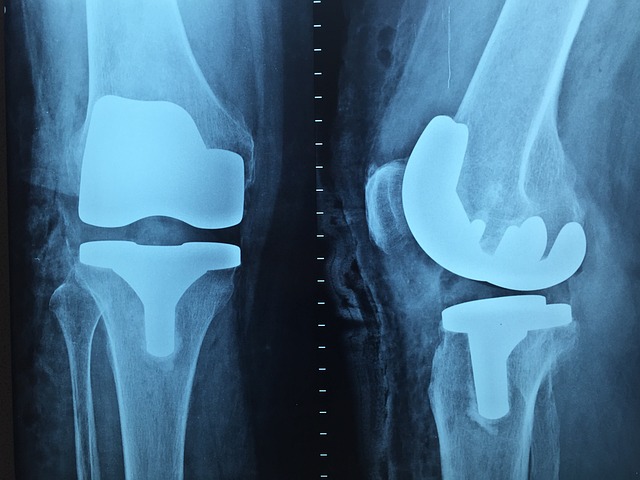

Cirugía Articular

Atendemos padecimientos en diferentes tipos de articulaciones como: hombro, codo, rodilla, cadera, etc., puede ser de manera conservadora (terapia) o con algún procedimiento quirúrgico con el que se busque recuperar el bienestar y movilidad del paciente.

Un ejemplo de este tipo de cirugías puede ser la implatación de alguna prótesis